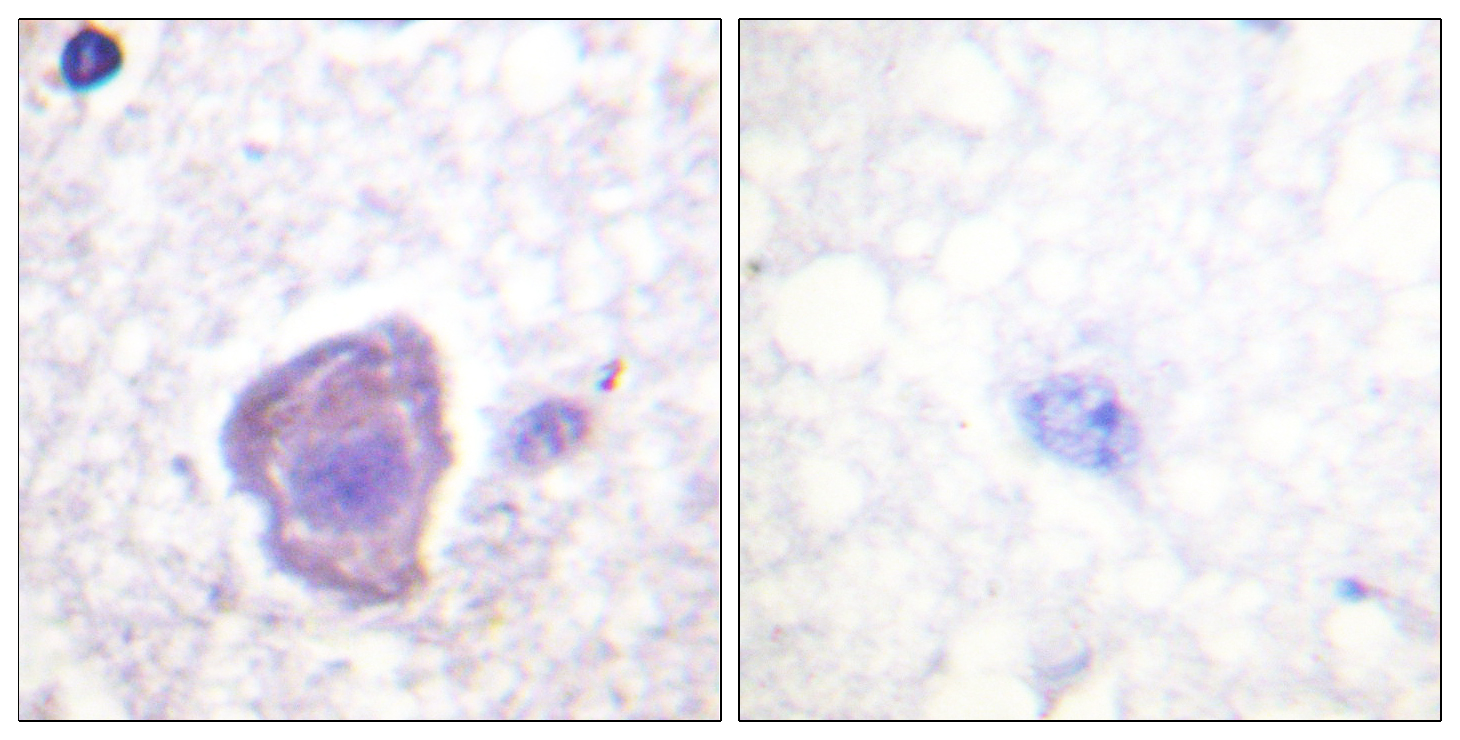

Anti-TAT AntibodyA98309

ApplicationsELISA, ImmunoHistoChemistry

ReactivityHuman, Mouse, Rat